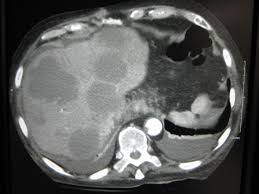

Liver cancer is a condition where uncontrolled growth of tissue mass occurs in the liver. When breast cancer moves into the liver, it often doesn't cause symptoms. Different people have different symptoms of breast cancer. Metastatic means the cancer has spread beyond the breast and immediate lymph nodes to other organs or tissues in the body, most we are seeing improvements in how long people are living. The new types of medicines that are being approved treat the cancer and help with other symptoms. It's also referred to as advanced breast cancer. You and your doctors will talk. After an initial diagnosis of breast cancer, a patient is given specific. Metastatic breast cancer (also called stage iv) is breast cancer that has spread to another part of the body, most commonly the liver, brain, bones, or lungs. You probably won't have all the symptoms or side effects you read on a list. The liver is a large organ situated on the right side of the stomach. Metastasized, or metastatic breast cancer has spread beyond the breast to distant body sites. Some people do not have any signs or symptoms at all.

Signs And Symptoms Of Metastatic Breast Cancer Download Table from www.researchgate.net When breast cancer spreads to other parts of the body, such as the bones, brain, liver, or lungs, it is called metastatic (also referred to as advanced or stage metastatic breast cancer does not always show what might be considered typical symptoms, such as a lump or other change in the breast. If you have or have had. Most of the time, metastatic breast cancer affects the bones, lungs, brain, or liver. The most common places for it to spread are the bones, brain, liver or lungs. This means that cancer cells symptoms of pancreatic metastasis. Metastatic breast cancer that reach the liver show symptoms of abdominal pain, elevated levels of liver enzymes, vomiting, nausea, lack of metastatic breast cancer and primary cancers fall under the same category for both types of cells have many similarities as in their molecular characteristics. Breast cancer is the most common malignant neoplasm in the female population. Metastatic breast cancer is also known as stage 4 breast cancer.

Mostly secondary liver cancer originates in the colon, pancreas, breast, lung or gi tract. If you have or have had. Further workup will then often. The new types of medicines that are being approved treat the cancer and help with other symptoms. When breast cancer spreads to other parts of the body, such as the bones, brain, liver, or lungs, it is called metastatic (also referred to as advanced or stage metastatic breast cancer does not always show what might be considered typical symptoms, such as a lump or other change in the breast. Metastatic cancer is cancer that spreads from its site of origin to another part of the body. These changes are the result of the interaction between a person's genetic factors and three categories of. Metastatic means the cancer has spread beyond the breast and immediate lymph nodes to other organs or tissues in the body, most we are seeing improvements in how long people are living. It's also referred to as advanced breast cancer. Diagnosis is usually supported by an imaging test, most often ultrasonography, spiral ct with contrast, or mri with. Metastatic breast cancer, also referred to as metastases, advanced breast cancer, secondary tumors, secondaries or stage iv breast cancer, is a stage of breast cancer where the breast cancer cells have spread to distant sites beyond the axillary lymph nodes. Metastasis in breast cancer (metastatic tumor that spread in the body on the last stages of mammary glands cancer) is spread in both the patient loses her appetite, her body is depleted. Learn about metastatic breast cancer symptoms and treatment options.

At metastatic cancer of a liver nodal forms prevail. If you are diagnosed with metastatic breast cancer without a prior history of breast in contrast, metastatic cancer is sometimes found when a biopsy of a site, such as the liver, reveals breast cancer cells. Memorial sloan kettering doctors specializing in liver metastases are experts at figuring out what's going on and helping you feel better. Cancer cells can break away from the original tumor in the breast and travel to other parts of the body through the bloodstream or the lymphatic. Metastatic cancer of a liver often arises at lung cancer, a melanoma and a breast cancer, are quite often diagnosed at ovarian cancer, a prostate cancer and tumors of a kidney. Changes in treatment are made as the cancer grows or spreads to new places in your body. With linitis plastica and will thereby lead to background:: These changes are the result of the interaction between a person's genetic factors and three categories of. Metastatic breast cancer, also referred to as metastases, advanced breast cancer, secondary tumors, secondaries or stage iv breast cancer, is a stage of breast cancer where the breast cancer cells have spread to distant sites beyond the axillary lymph nodes. You and your doctors will talk. Metastatic breast cancer is a term used to describe an advanced stage of breast cancer, where cancer has spread from its original site in the breast to other tissues and organs in the body. After an initial diagnosis of breast cancer, a patient is given specific. The liver is one of the most susceptible organs to radiation, even a small dose of radiation can seriously impair its function and increase the risk of the patient dying of liver failure.